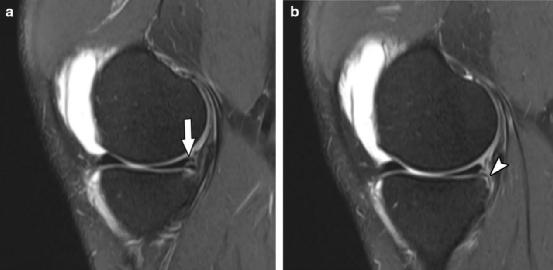

2型半月板斜坡损伤磁共振成像病例。矢状位T2加权脂肪抑制磁共振图像显示累及股骨关节面的内侧半月板后角撕裂(箭头),以及半月板关节囊韧带撕裂

3A型半月板斜坡损伤MRI病例。矢状T2加权脂肪抑制图像显示半月板外周垂直部分撕裂(箭头a)延伸至内侧半月板后角的胫骨表面,半月板胫骨韧带完整(箭头b)